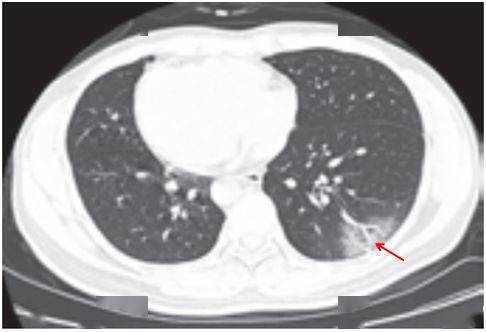

(一)病灶分布

病灶以 肺外围背侧为主,以两肺下叶为著,与胸膜常紧贴,提示新冠肺炎病变多首先侵犯皮层肺组织的细支气管及肺泡上皮, 病灶分布逐步从外周向中央扩展(图 2-1)

图2-1 早期病灶多数分布贴近胸膜( 共4张 )